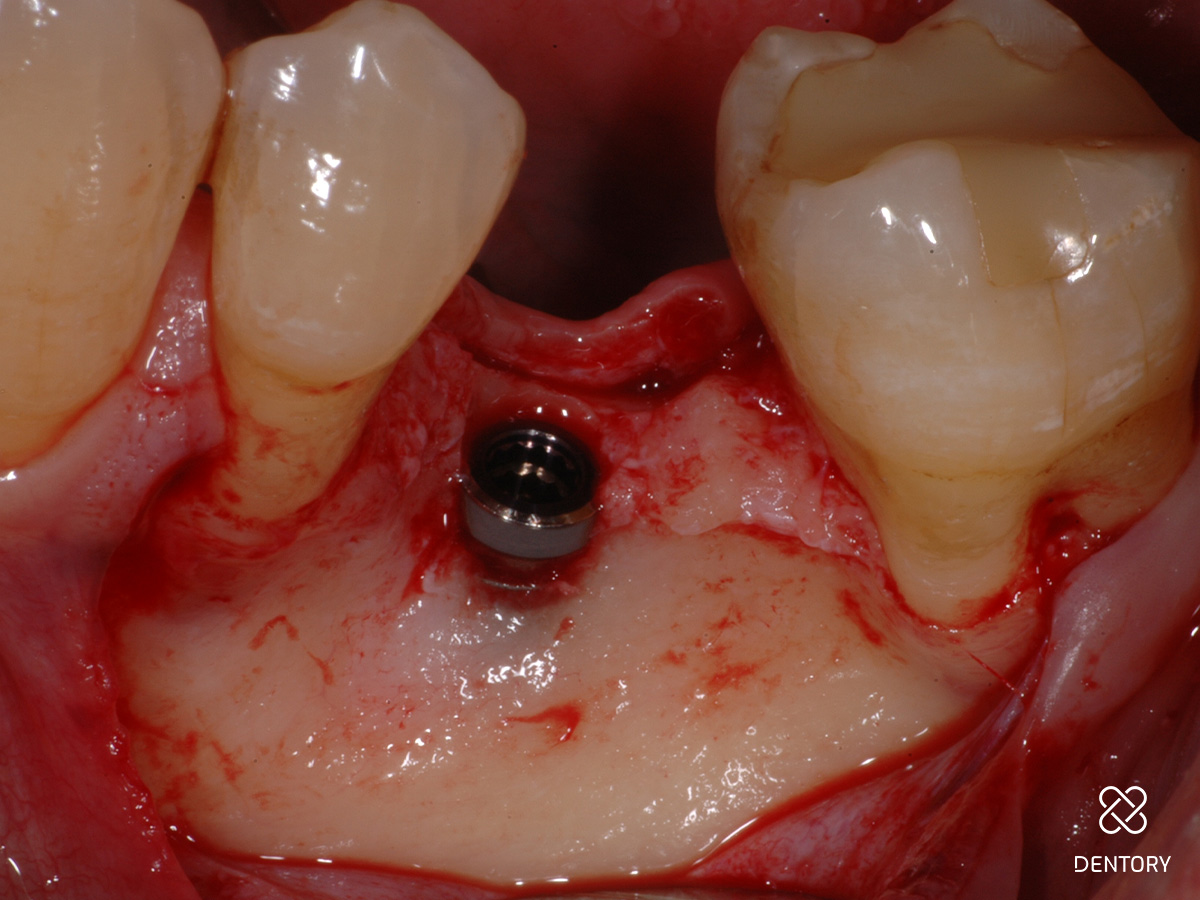

Abbildung 4

In der Lateralansicht zeigt sich ein moderater Dehiszenzdefekt bei gut erhaltener Knochenstruktur an den Nachbarzähnen, welche die Knochenregeneration unterstützen werden.